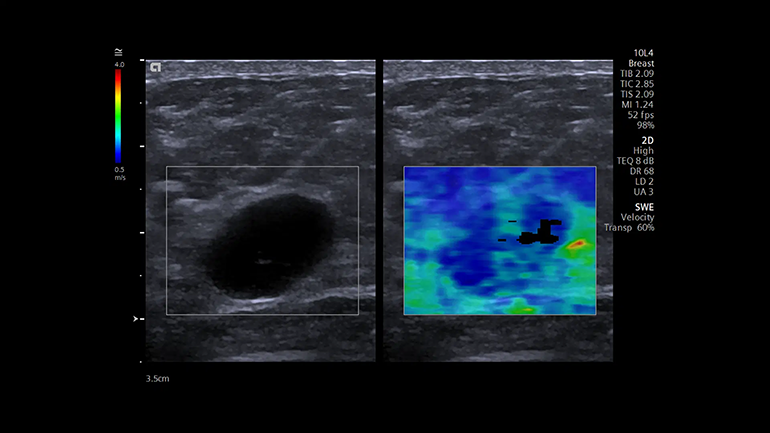

Технология качественного определения жесткости ткани в зоне интереса Point Shear Wave (pSWE). Технология точечной эластографии со сдвиговой волной позволяет получать воспроизводимую, надежную и подробную информацию о жесткости исследуемой ткани и помогает в оценке состояния, например, печени. Технология для определения скорости распространения поперечной волны при работе с линейными и конвексными датчиками. Двумерная эластография со сдвиговой волной (SWE). Это технология качественной и количественной диагностики, с помощью которой можно получить цветовые карты жесткости тканей молочной и щитовидной желез, используя для этого датчик 10L4, а также конкретные цифровые значения скорости распространения поперечной волны.

Технология для определения скорости распространения поперечной волны при работе с линейными и конвексными датчиками. Двумерная эластография со сдвиговой волной (SWE). Это технология качественной и количественной диагностики, с помощью которой можно получить цветовые карты жесткости тканей молочной и щитовидной желез, используя для этого датчик 10L4, а также конкретные цифровые значения скорости распространения поперечной волны. Технология визуализации эластичности ткани с использованием мануальной компрессии для линейных датчиков. Метод мануальной деформационной эластографии Virtual Touch обеспечивает простое и качественное измерение жесткости пораженного участка относительно окружающих неповрежденных тканей.